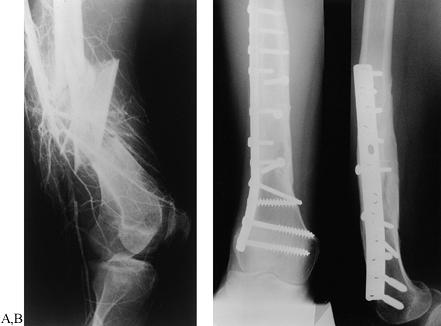

Figure 20.10. Plate fixation of a femur fracture. A:

Lateral radiograph showing a comminuted mid-shaft grade IIIC open femur

Postoperative AP and lateral radiographs. The artery has been repaired,

and the femur has been fixed with interfragmentary screws and a broad

plate. -